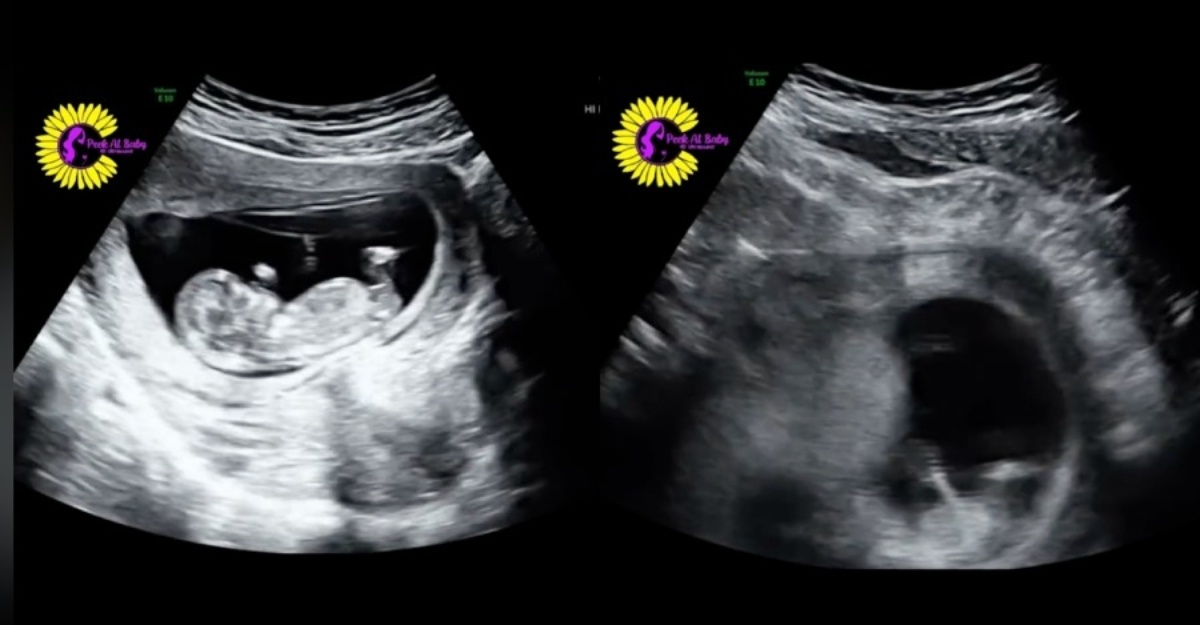

Sonografi Dedah Keadaan Bayi Dalam Kandungan Ketika Ibu Ketawa

Bayi ‘bergoncang’ ketika ibu ketawa, sonografi dedah keadaan dalam kandungan

Dalam pada itu, @nypost baru-baru ini telah berkongsi seorang ibu hamil di Yukon, Oklahoma mengalami detik unik apabila rakaman ultrabunyi menunjukkan bayinya bergerak semasa dia ketawa dengan kuat.

Video berdurasi 00:34 saat turut menunjukkan apabila si ibu ketawa, otot perutnya mengecut dan menyebabkan sedikit tekanan pada rahim yang boleh membuatkan bayi seolah-olah ‘terhimpit’.

Bagaimanapun, posisi bayi dalam kandungan dilihat kembali seperti biasa ketika si ibu mula berhenti ketawa.